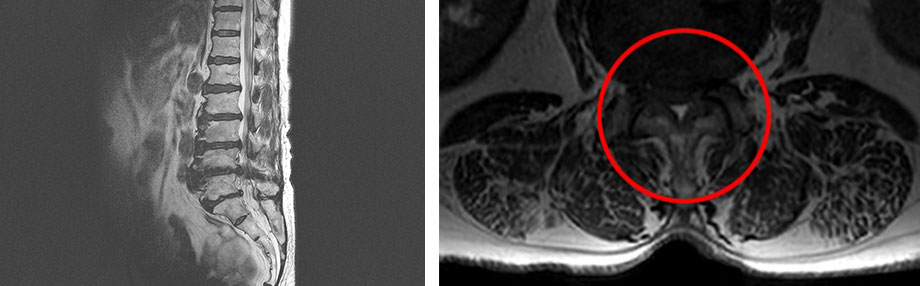

(척추 여러 레벨이 심하게 퇴행되어 있고,

척추관의 공간이 거의 막혀 있어 다리로 가는 신경을 압박하여

정상적인 보행이 어려워짐)